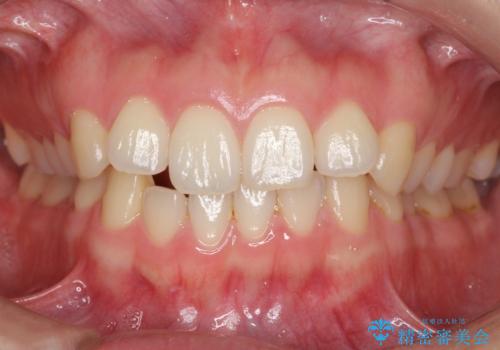

上下前歯が接触しない オープンバイトをインビザラインで改善

オープンバイト(開咬)を非抜歯インビザラインで治す